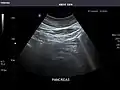

Pancreas

Pancreas: Visualized portions unremarkable.